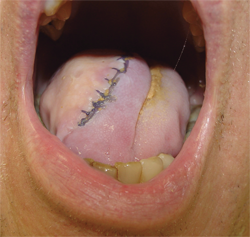

Myocutaneous flaps are frequently used in the reconstruction of head and neck defects after surgical resection. The use of muscle provides bulk and protection for the surgical area. The bulk and constriction in the head and neck area limits the use of pedicle flaps (flaps that maintain their native blood supply). In addition, pedicle flaps do not achieve the cosmetic goal. There fore, myocutaneous free flaps are often used to reconstruct the tongue, floor of the mouth, and the upper portion of the esophagus that connects to the larynx. A free flap must have vessels connected in the new area to provide new blood supply to this completely removed and re attached muscle. A portion of the quadriceps muscle, the anterolateral thigh flap, can be used and formed into a tube to reconstruct the top of the esophagus.1 The workhorse muscle for the head and neck region is the radial forearm free flap. This muscle tends to be the optimal size and thickness to replace the resected portion of the tongue, for example, after a hemiglossectomy (Figure 2). Without use of a major portion of the tongue, a patient’s speech and swallowing are affected. Patients are unable to speak clearly and are not able to propel the food into the back of the throat to be swallowed.3,6